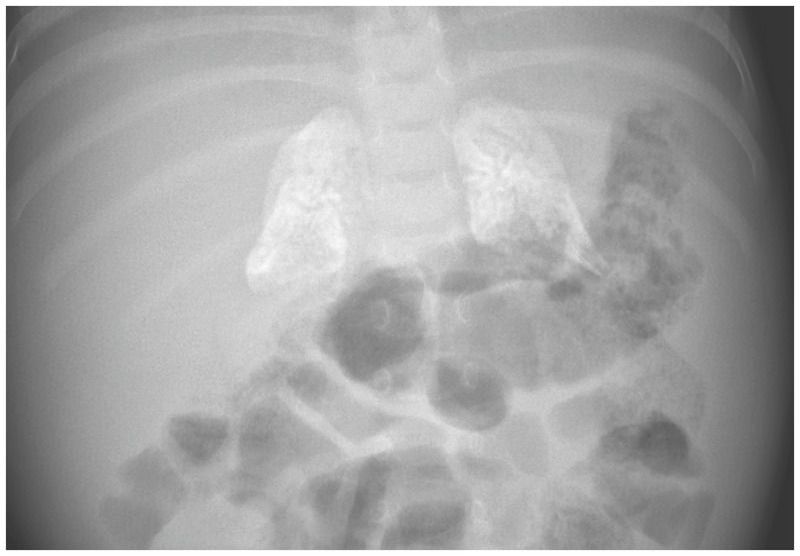

A 4-month-old girl was admitted to the hospital with failure to thrive. After an uncomplicated prenatal course and delivery, she had a normal birth weight of 3350 g. However, at 4 months of age her weight was only 4090 g (z score, −3.5). She was fed a cow’s milk–based formula, and although she had no diarrhea or vomiting at the time of admission, diarrhea developed within a few days after admission. The parents had two other daughters, and both were healthy. Physical examination of the infant revealed a protuberant abdomen with an enlarged liver and spleen. Blood tests showed normocytic anemia, elevated levels of liver aminotransferases, and hyperlipidemia. Plain radiography of the abdomen revealed calcification of both adrenal glands. A dried blood-spot test for enzyme activity was performed and indicated lysosomal acid lipase deficiency. A homozygous mutation in LIPAwas identified on gene sequencing, which confirmed the diagnosis of lysosomal acid lipase deficiency, or Wolman’s disease, an autosomal recessive metabolic condition. Because lysosomal acid lipase is critical for the metabolism of cholesteryl esters and triglycerides, a deficiency leads to lipid accumulation in the liver, spleen, and gut, which causes malabsorption and growth failure, and to calcification of the adrenal glands. Genetic counseling was provided, and the infant was treated with recombinant human lysosomal acid lipase. A low-fat formula and parenteral nutrition were provided. The patient’s growth began to improve, and at 9 months of age she weighed 6500 g (z score, 2.6). Her development is steadily improving, but psychomotor delay is still present.